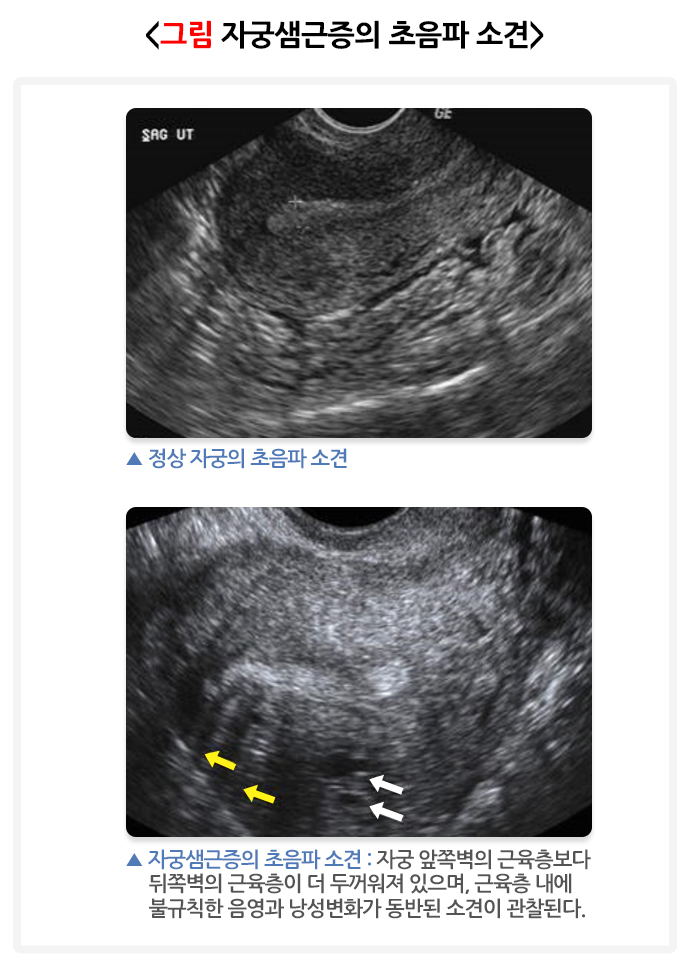

자궁샘근증을 진단하기 위해서 산부인과적 신체진찰이 먼저 시행되어야 합니다. 월경과다, 비정상 자궁출혈, 심한 월경통 등의 증상을 호소하는 여성에서 내진 시 전반적으로 자궁의 크기가 증가되어 있고 단단한 느낌이 들면서 압통이 동반된 소견을 보이면 자궁샘근증을 추정할 수 있습니다. 이후 초음파나 자기공명영상(MRI) 촬영에서 자궁샘근증에 합당한 소견을 보이면 임상적으로 진단할 수 있습니다. 하지만 최종적으로 자궁샘근증을 확진하기 위해서는 수술을 시행하여 병리학적 소견에 의한 진단이 필요합니다.

자궁근종은 초음파에서 경계가 명확하게 보이는 데 반해, 자궁샘근증은 경계가 명확하지 않습니다. 그러나 자궁근종과 감별이 어려운 경우도 있어 자궁샘근증을 가진 많은 여성들이 자궁근종을 가지고 있는 것으로 오해하는 경우도 있습니다. 그러나 자궁근종과 자궁샘근증은 완전히 다른 질환으로, 질병의 치료 역시 다르게 접근해야 합니다. 따라서 정확한 진단이 매우 중요합니다.